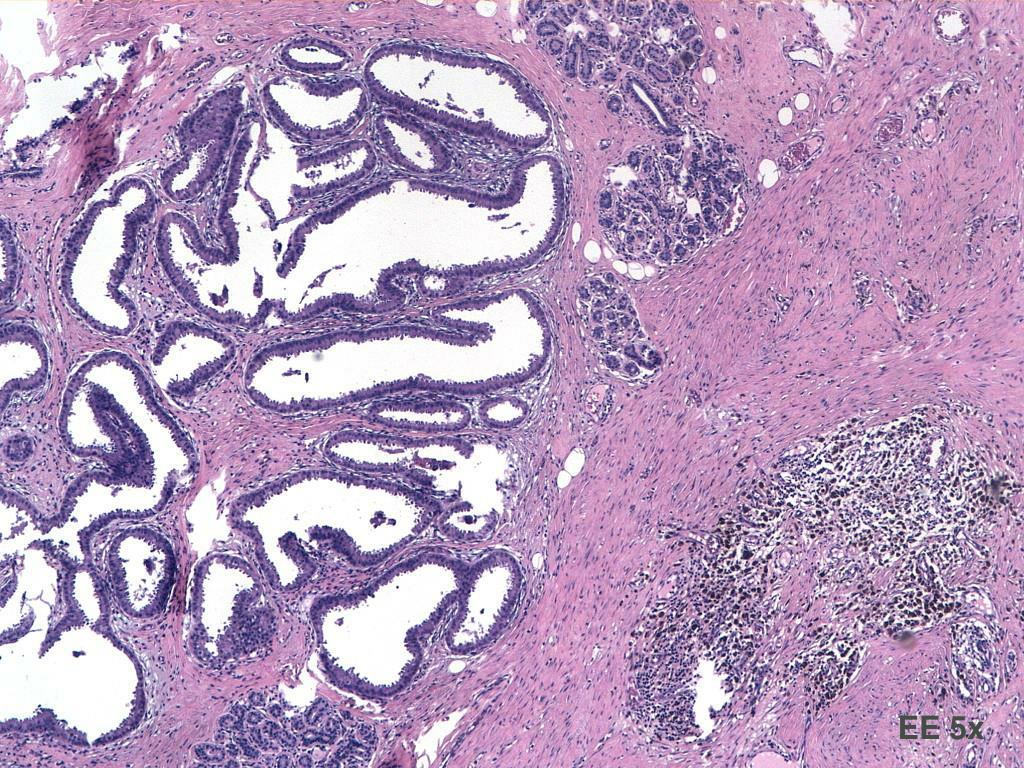

2. L.D., 50 anni,microcalcificazioni QIE dx

3. EE 10x EE 10x

10. DIAGNOSI. Parenchima mammario con focolai di iperplasia dutto-lobulare a fisionomia apocrina con lieve atipia e necrosi intraduttale, associata a calcificazioni grossolane. Focale, puntiforme e irregolare positività per proteina p63, proteina 100 e actina 1A4. DIN1b/DIN1c (IDA/DCIS BG)